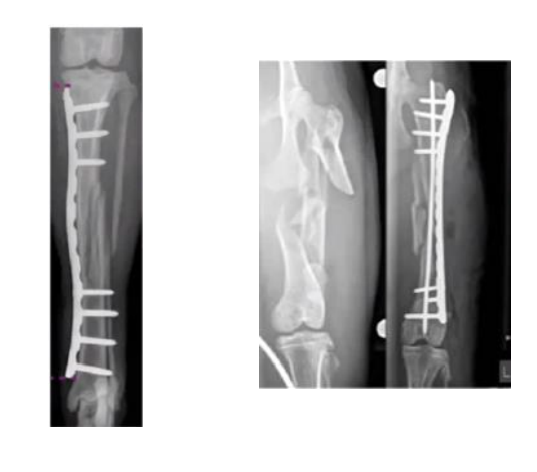

Métodos de inmovilización

Entablillado de extremidad

Férulas y vendajes.

Entablillado del hueso

- Fijador esquelético externo

- Clavo intramedular

- Placa de hueso

Compresión

- Tornillo LAG

- Cerclaje / interfragmentario

- Banda de tensión